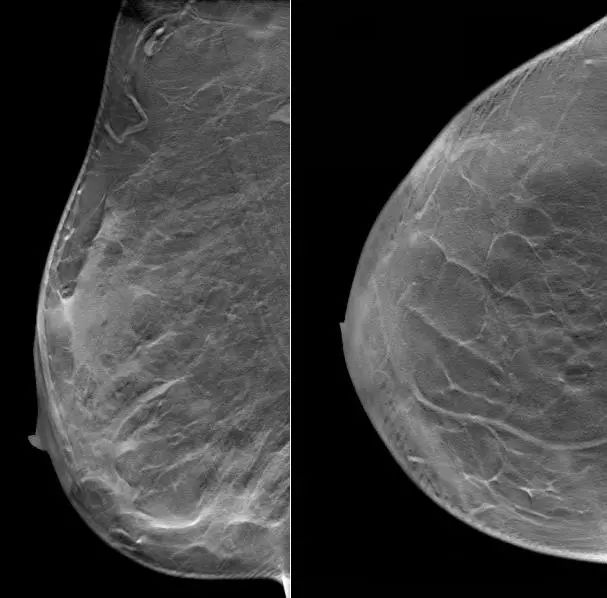

2021.7.6 钼靶示:右乳外上象限肿块,考虑乳腺癌(BI-RADS-5类)右腋下肿大淋巴结,M灶可能。

右乳外上象限不规则高密度肿块,边缘毛糙,大小约3.3×2.7cm,邻近皮肤牵拉增厚,右腋下见肿大淋巴结。

图2. 钼靶

(3 cycle 后)2021.9.21 钼靶示:右乳外上象限不规则形肿块明显缩小,右腋窝淋巴结亦较前缩小。

图6. 钼靶